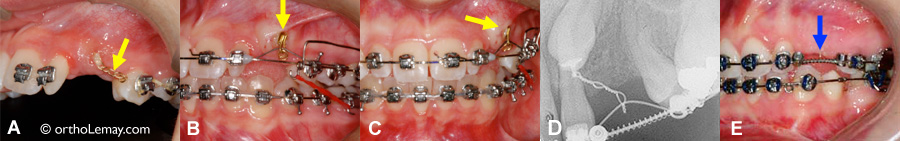

(A) Au début de la traction, les anneaux de la chaînette sont visibles hors de la gencive. (B et C) Une fois la canine rendue près de la surface, la chaînette est coupée et un fil ou autre mode de traction peut être engagé directement dans l’attache collée sur la surface de la canine. (D et E) Malgré une chaînette assez longue (visible sur une radiographie), ce qui paraît en bouche est très minime et pratiquement invisible.

Esthétique

(A) La radiographie permet d’apprécier la longueur de la chaînette de traction enfouie dans la muqueuse du palais. (B) Une petite partie de la chaînette sort de la gencive pour s’attacher au fil de l’arcade. (C et D) Des dents artificielles fixées sur des brackets attachés au fil camouflent l’espace où seront les canines ainsi que la chaînette.